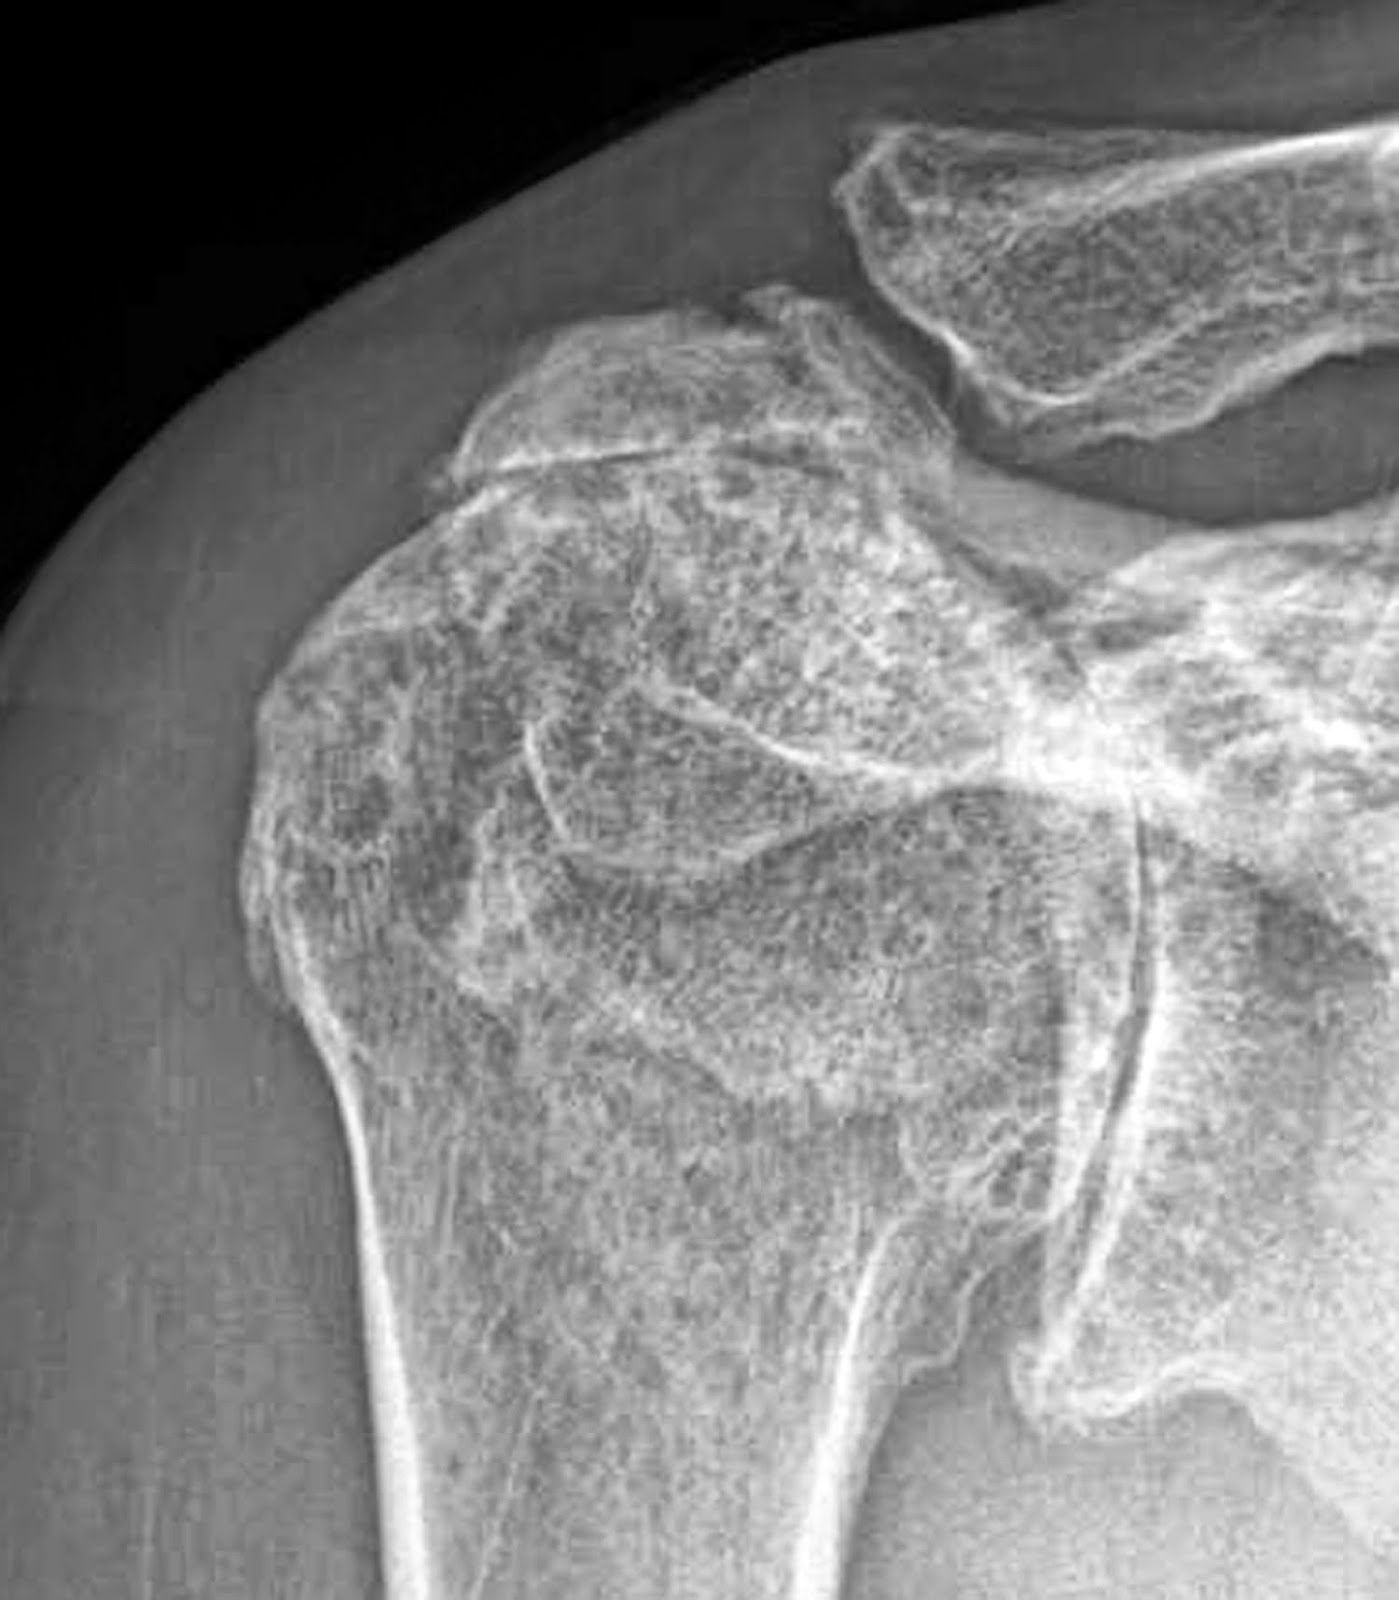

From www.researchgate.net

Rotator cuff tear arthropathy. (a) Conventional Xray, (b Rotator Cuff Tear From Dislocation Conservative treatments — such as rest, ice and physical therapy — sometimes are all that's needed to recover from a rotator cuff. Rotator cuff tears are a very common source of shoulder pain and decreased motion that can occur due to both traumatic injuries in young patients as well as. Next to the number of tendons which are torn, at. Rotator Cuff Tear From Dislocation.